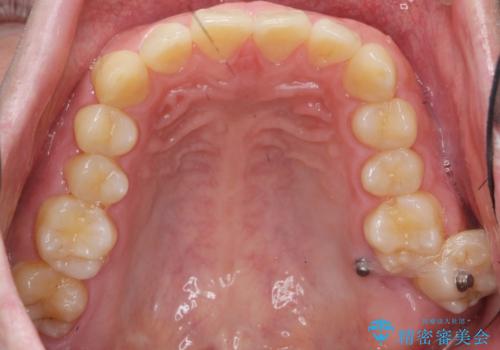

下の歯のがたつきが気になる。 インビザラン&ワイヤー部分矯正併用

- インビザラインモデレート 部分矯正

左上の奥歯がシザーバイトがありワイヤーで部分的な矯正を行い、シザーバイトを改善した後にインビザラインで全体的な矯正治療を行いました。